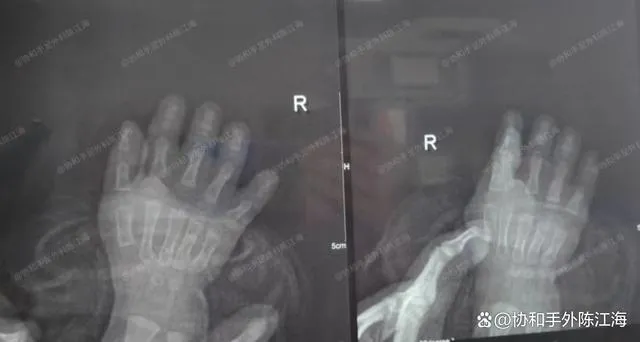

Dette barn har Polen-syndrom, en ret unik deformitet, der er karakteriseret ved både korte og syndaktyliske (vævede fingre) træk, hvilket i væsentlig grad påvirker både udseende og funktion. I en alder af 11 måneder blev barnet opereret. Under denne opfølgning i en alder af 2 et halvt var hendes hænder vokset betydeligt større, og hun kunne nu gribe større genstande.

Røntgen